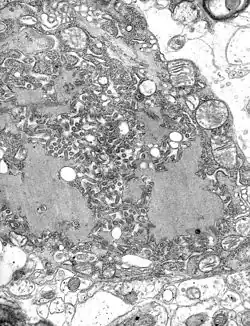

TEM-Aufnahme einer infizierten Zelle. | ||||||||||||||||||||

Die Transkription und Replikation finden im Zytoplasma der Wirtszelle innerhalb spezieller „Virenfabriken“ (VF, auch Viroplasmen) statt, die lichtmikroskopisch als sogenannte Negri-Körper bezeichnet werden (benannt nach Adelchi Negri). Sie haben einen Durchmesser von 2–10 µm und sind typisch für die Tollwutinfektion, so dass sie als pathognomonisches Merkmal dienen.[4]